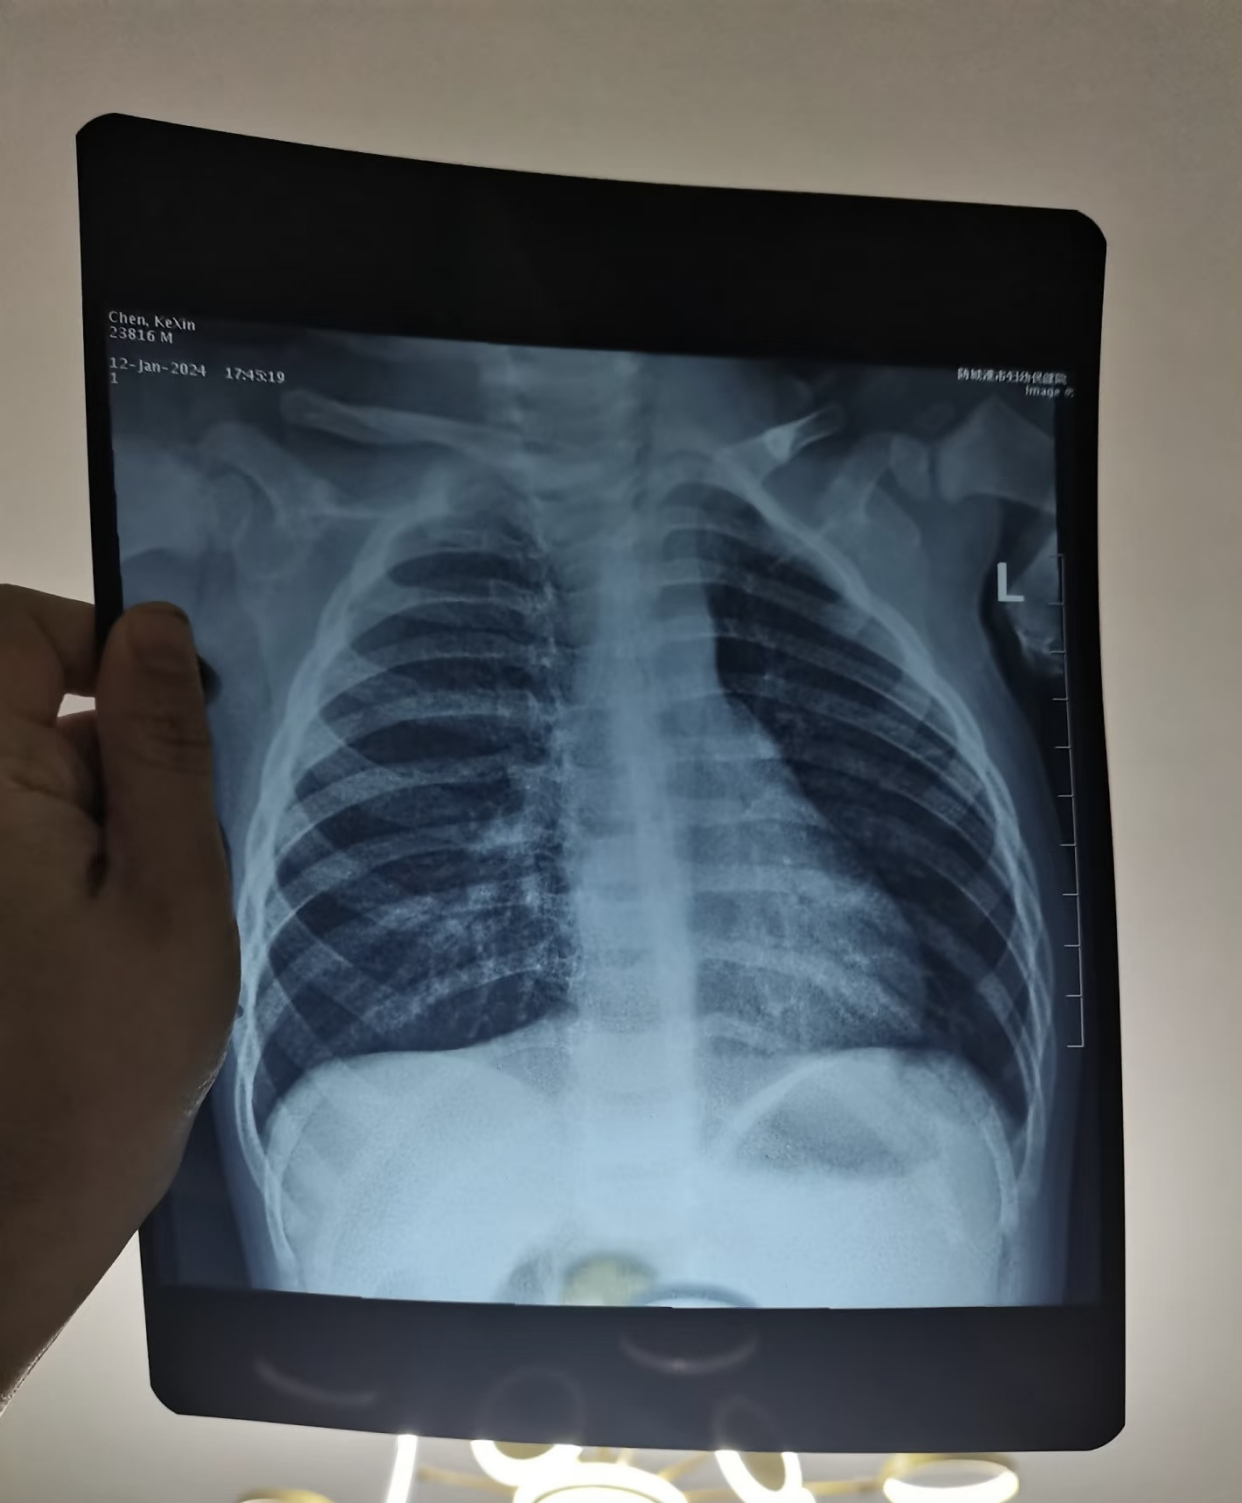

大神们看看,有肺炎么?

图1这个小姑娘4岁,咳嗽发热5天, x光片发现右侧大叶性肺炎